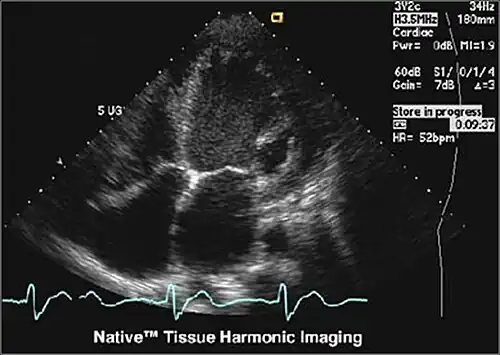

Tissue Harmonic Imaging

Tissue Harmonic Imaging (THI) ist ein Verfahren in der medizinischen Ultraschallbildgebung, das vor allem die Kontrastauflösung, aber auch die räumliche Auflösung erhöht. Grundsätzlich wird dabei Ultraschall mit einer Frequenz („Grundwelle“ oder „1. Harmonische“) in das Gewebe gesendet und die Signale mit der doppelten Frequenz, also („Oberwelle“ oder „2. Harmonische“) für die Bildgebung verwendet, die durch die nichtlineare Ausbreitung im Gewebe entstehen.

Häufig ist das Fettgewebe an der Körperoberfläche die Ursache für störende Artefakte. Da die Oberwellen erst mit der Ausbreitung im Gewebe zunehmen, sind Bilder, die aus diesen Frequenzen erstellt werden, frei von diesen Artefakten. Darüber hinaus ist die räumliche Auflösung höher, weil die Frequenz höher ist.